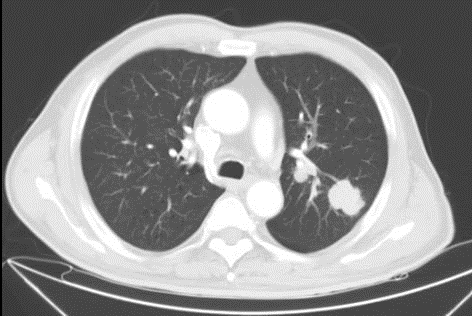

2022-08-04颅脑MRI:右侧小脑半球、右侧额颞顶枕叶及左侧放射冠区异常密度影,考虑多发占位性病变。

图1.首诊颅脑MRI